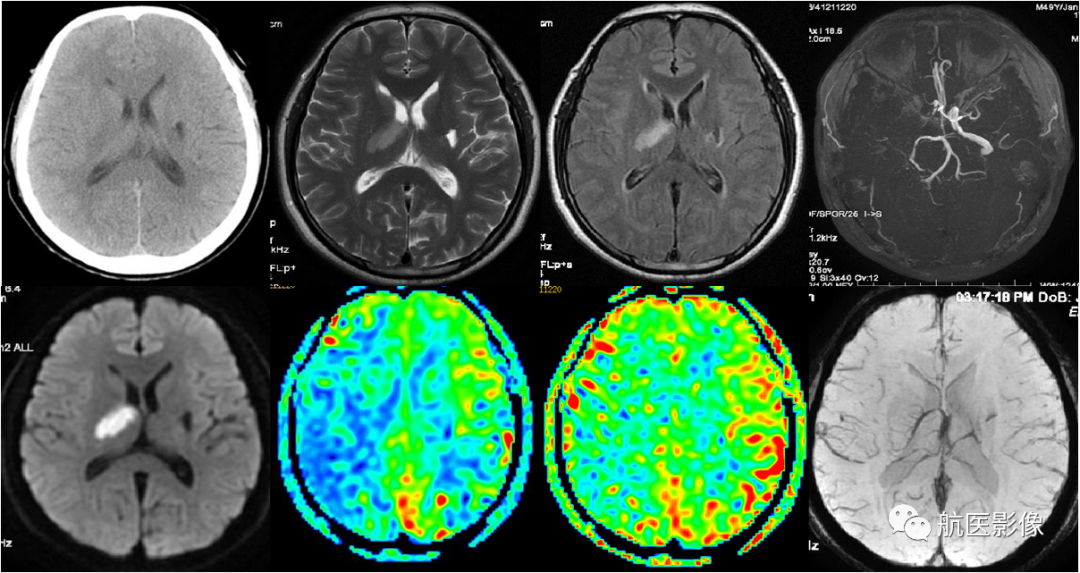

2.脑血管病MR多模态检查:

DWI序列对早期脑梗死的诊断具有较高的敏感性; SWI序列可以检测颅内微出血,对指导临床治疗具有重要作用; 3D-ASL序列可评估脑侧支循环; MRA不需要注射造影剂即可进行脑血管成像。